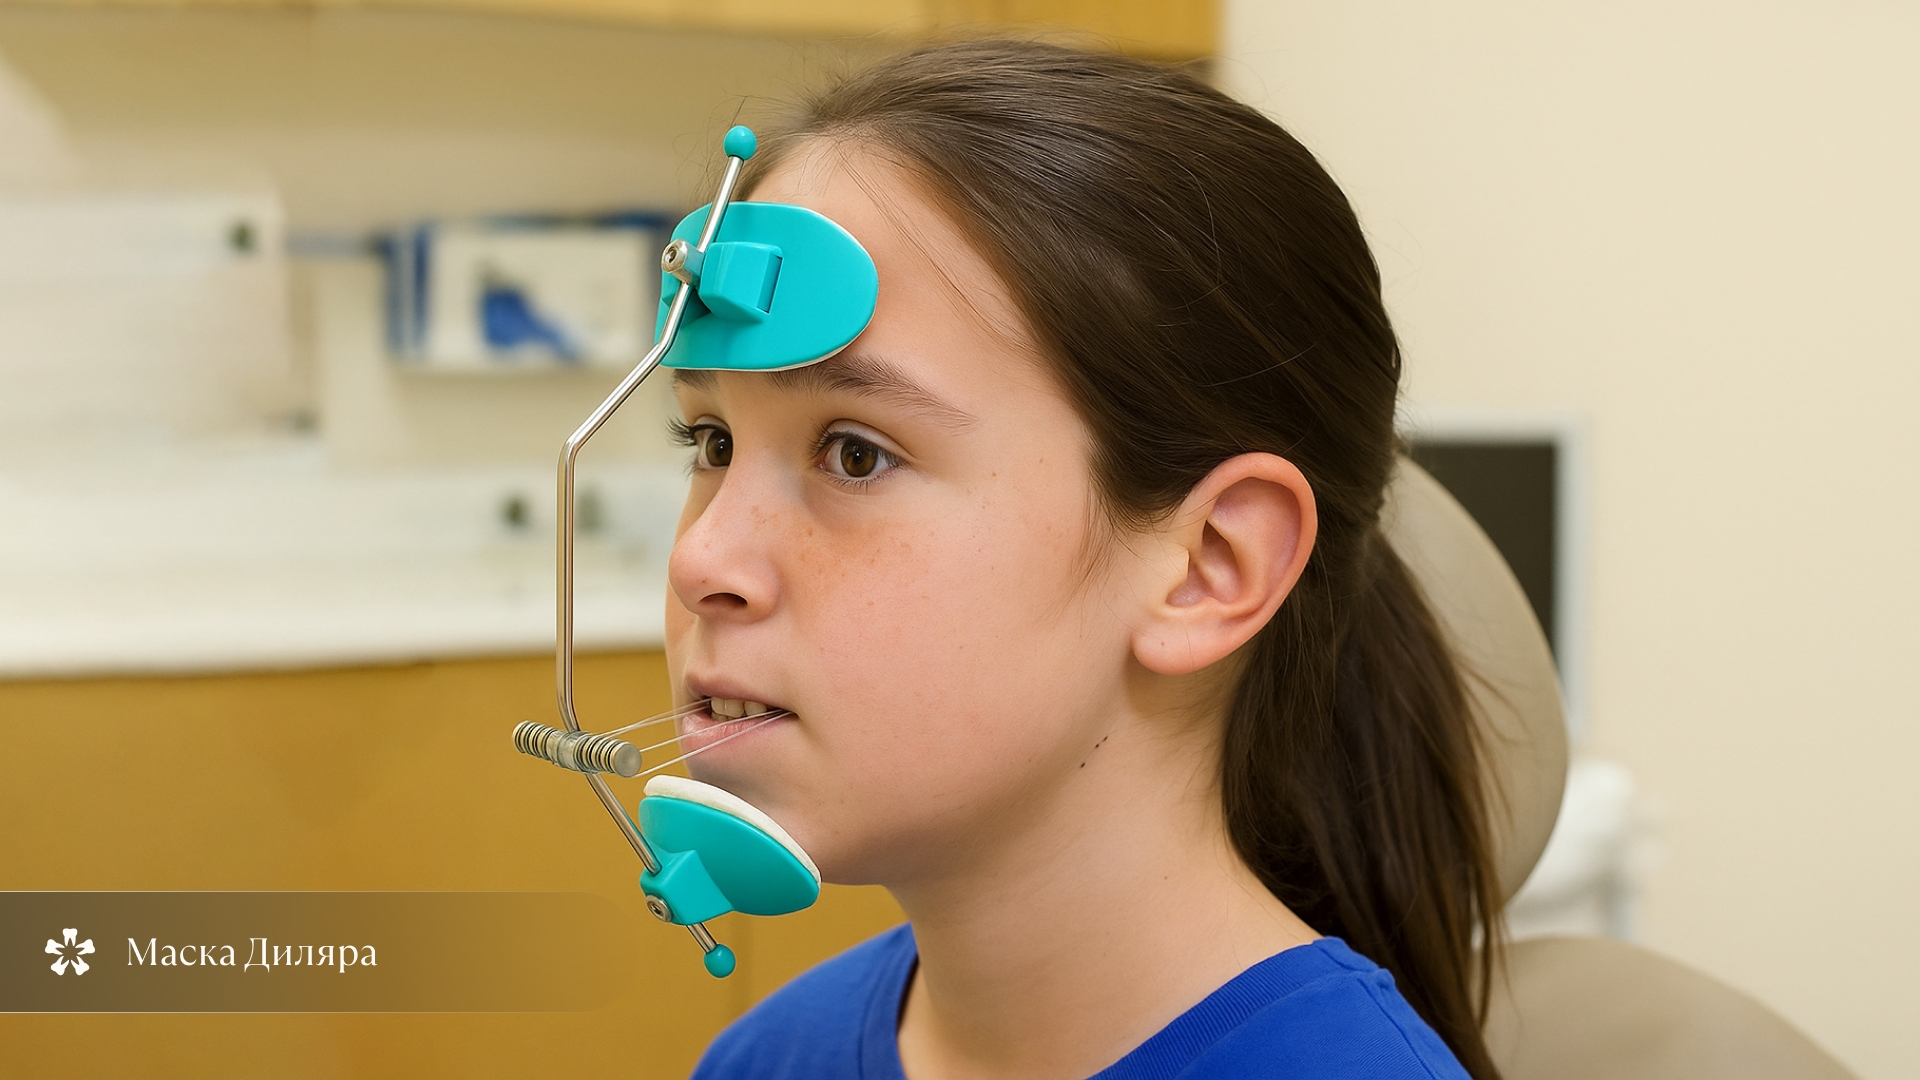

| 6–9 лет | Маска Диляра, аппарат Френкеля |

Маска Диляра

Маска Диляра — это внеротовой аппарат, состоящий из вертикальной металлической дуги. На одном конце дуги есть лобный упор, на другом — подбородочный упор, и между ними находится небольшая горизонтальная дуга, к которой фиксируются тяги от крючков, фиксирующихся в полости рта. Лицевая маска используется при недоразвитии верхней челюсти для стимуляции её роста, также в некоторых случаях ее можно применять для перемещения верхних боковых зубов вперед. Чаще маску назначают детям до 10 лет. Метод дает быстрый результат, но требует носить конструкцию по 14–16 часов в день. В начале может появиться легкое раздражение кожи в месте фиксации. Лечение занимает от полугода до года, стоимость — от 15 тысяч рублей.